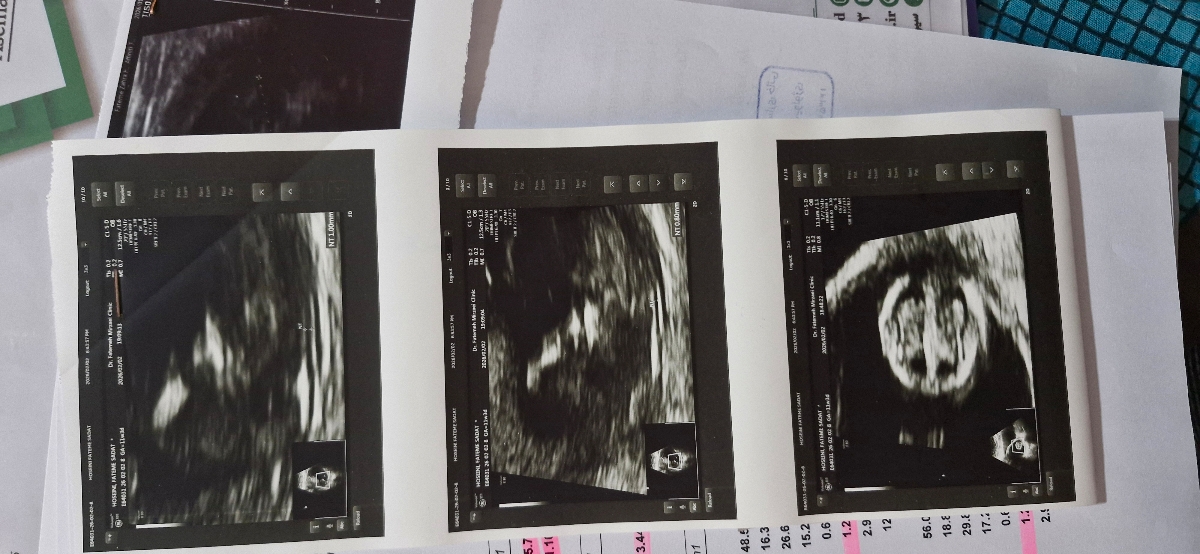

سلام دکتر جان وقت بخیر دیروز رفتم سونو ان تی دادم ،

میشه سونو رو بررسی کنید

جنسیت هم چیزی بهم نگفت میخواستم ببینم جنسیت بچه از روی عکس مشخص میشه؟

پزشک اوما

سلام به روی ماهتون مامان جان

وقتتون بخیر

نه جانم جنسیت از روی عکس مشخص نمیشود هغته 18 زمان تعیین جنسیت با سونوگرافی است صبوری کنید

درمورد دردتان اگر الان درد ندارید جای نگرانی نیست

در سونوگرافی ارسالی همه چیز عالی است و مشکلی ندارد فقط جهت تفسیر صحیح باید منتظر بخش خون غربالگری باشیم

طول سرویکس هم در محدوده ای است که باید بیشتر محتاط باشید کار سنگین نکنید پیاده روی طولانی نکنید استراحت کافی داشته باشید نزدیکی محدود باشد

از سرویس بهداشتی فرنگی استفاده نمایید

فکر میکنم عکستان کامل نیست چون جایگاه جفت در این برگه ها مشخص نیست